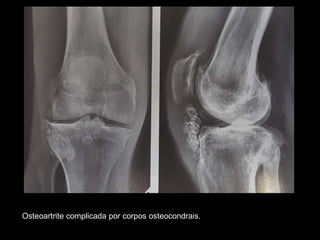

Osteoartrose complicada por corpos osteocondrais. Radiografias de homem de 66 anos

com osteoartrose avançada demonstram o envolvimento dos compartimentos

femorotibial medial e femoropatelar, com a formação de dois grandes corpos

osteocondrais.

Osteoartrite complicada por corpos osteocondrais.